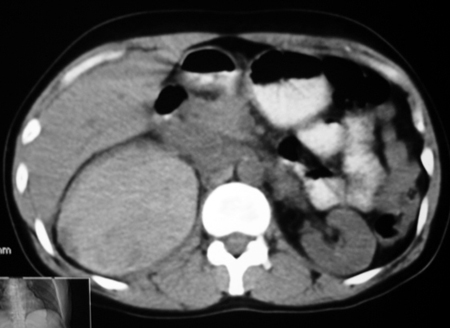

以下是引用卜一在2009-4-23 15:43:00的发言:[br]考虑右肾包膜下血肿,不排除占位病变伴出血可能,建议进一步检查。